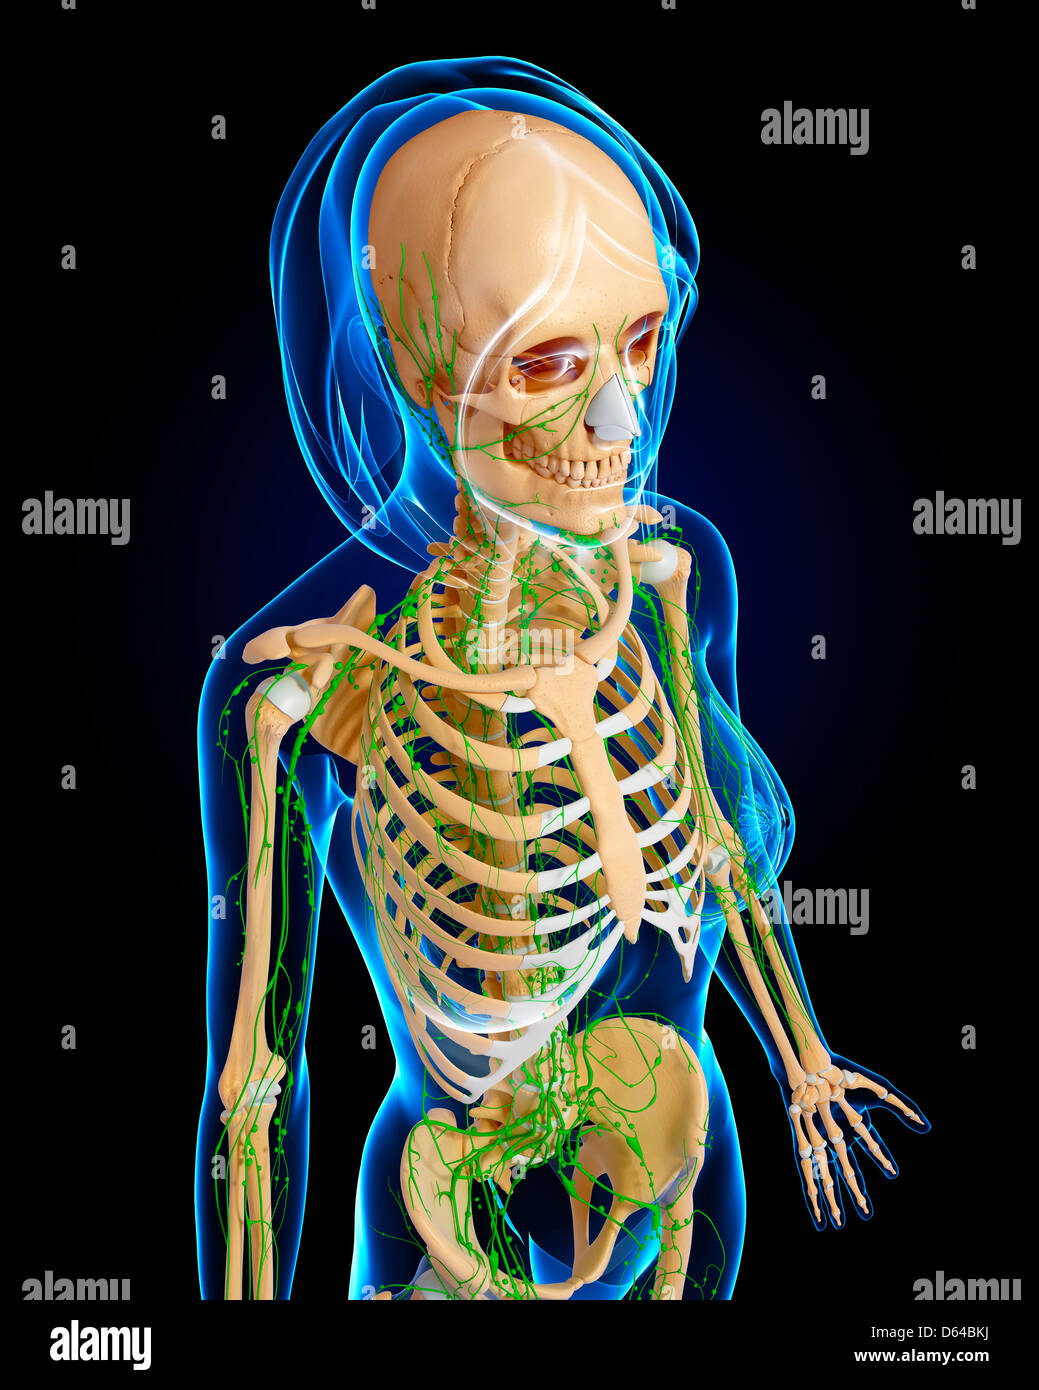

female anatomy art Complete female anatomy 3d model

fineartamerica.comFemale Anatomy, Artwork Stock Photo - Alamy

fineartamerica.comFemale Anatomy, Artwork Stock Photo - Alamy

fineartamerica.comFemale Anatomy, Artwork Stock Photo - Alamy

fineartamerica.comFemale Anatomy, Artwork Stock Photo - Alamy

www.alamy.comFemale Anatomy, Artwork Stock Photo - Alamy

www.alamy.comFemale Anatomy, Artwork Stock Photo - Alamy

bocadowasubo.github.ioFemale Anatomy, Artwork Stock Photo - Alamy

bocadowasubo.github.ioFemale Anatomy, Artwork Stock Photo - Alamy

fineartamerica.comFemale Anatomy, Artwork Stock Photo - Alamy

fineartamerica.comFemale Anatomy, Artwork Stock Photo - Alamy

www.etsy.comFemale Anatomy, Artwork Stock Photo - Alamy

www.etsy.comFemale Anatomy, Artwork Stock Photo - Alamy

www.alamy.comFemale Anatomy, Artwork Stock Photo - Alamy

www.alamy.comFemale Anatomy, Artwork Stock Photo - Alamy

www.alamy.comFemale Anatomy, Artwork Stock Photo - Alamy

www.alamy.comFemale Anatomy, Artwork Stock Photo - Alamy

fineartamerica.comFemale Anatomy, Artwork Stock Photo - Alamy

fineartamerica.comFemale Anatomy, Artwork Stock Photo - Alamy

Female Anatomy, Artwork Stock Photo - Alamy

www.alamy.comFemale Anatomy, Artwork Stock Photo - Alamy

www.alamy.comFemale Anatomy, Artwork Stock Photo - Alamy

www.etsy.comFemale Anatomy, Artwork Stock Photo - Alamy

www.etsy.comFemale Anatomy, Artwork Stock Photo - Alamy

www.alamy.comFemale Anatomy, Artwork Stock Photo - Alamy

www.alamy.comFemale Anatomy, Artwork Stock Photo - Alamy

www.alamy.comFemale Anatomy, Artwork Stock Photo - Alamy

www.alamy.comFemale Anatomy, Artwork Stock Photo - Alamy

Female Anatomy, Artwork Stock Photo - Alamy

pixels.comFemale Anatomy, Artwork Stock Photo - Alamy

pixels.comFemale Anatomy, Artwork Stock Photo - Alamy

www.alamy.comFemale anatomy art print women body torso drawing illustration modern. Female anatomy photograph by pixologicstudio/science photo library. Female anatomy, artwork stock photo

www.alamy.comFemale anatomy art print women body torso drawing illustration modern. Female anatomy photograph by pixologicstudio/science photo library. Female anatomy, artwork stock photo